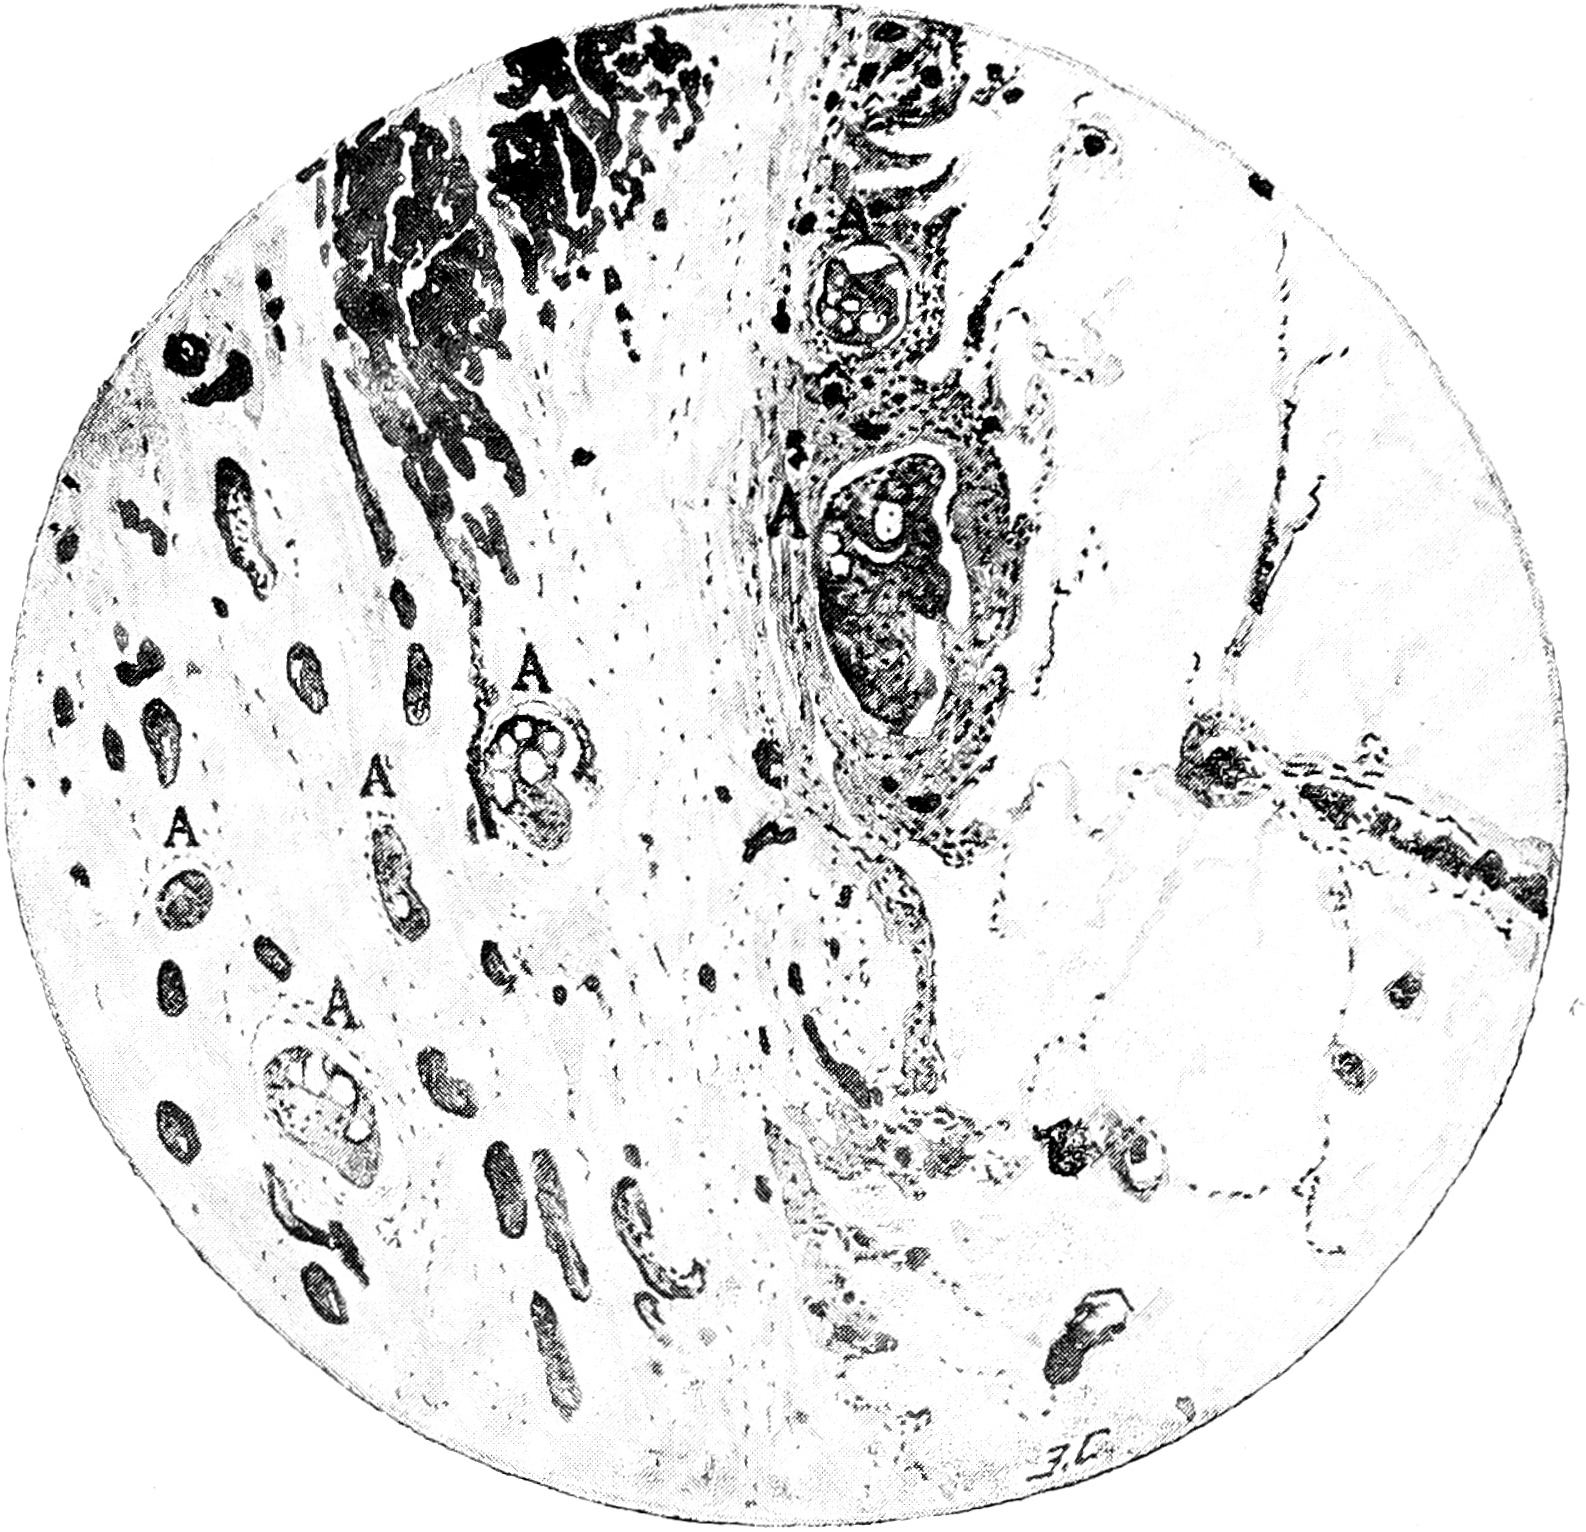

В этой соединительной ткани, служившей, таким образом, стромой для опухоли, залегали немногочисленные альвеолы с клетками новообразования (рис. 1). Альвеолы имели круглые, овальные или вытянутые очертания; реже они принимали неправильную форму, которая чаще всего возникала вследствие слияния нескольких рядом лежащих альвеол. Клетками новообразования нацело были выполнены только небольших размеров альвеолы. В более массивных альвеолах среди клеток новообразования существовало обильное количество различной величины полостей, казавшихся или пустыми, или выполненных нежно-струйчатой массой. Форму клеток возможно было наблюдать лучше всего в очень мелких альвеолах,—очевидно, недавно возникших. Здесь клетки чаще были полиэдрическими, реже овальными, круглыми. В наружных слоях они нередко принимали кубическую или даже невысокую цилиндрическую форму. Протоплазма клеток довольно светлая, нежнозернистая, ядра круглой или овальной формы, нерезко окрашивавшиеся. По мере увеличения размеров альвеол и возникновения среди клеток полостей, границы между отдельными клетками исчезали, вследствие чего возникала сплошная синцитиальная масса, в которой без всякого порядка залегали ядра. Очевидно, такое слияние протоплазмы являлось результатом дегенерации клеточных элементов, так как ядра принимали неправильные очертания и густо пикнотически окрашивались. Распределение ядер в этой общей массе протоплазмы было также своеобразно: в одних местах они густо сгруппировались, в других—значительные пространства протоплазмы не имели ядер.

Рис. 1

Рис. 1. Слева висцеральная плевра, справа ткань легкого. В плевре заметны 4 неправильно-овальных альвеолы, выполненных клетками новообразования. Reichert, Ob. 3, Ок 2.